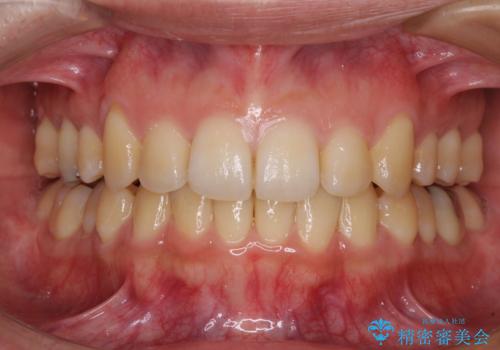

- 下顎の歯列から飛び出した小臼歯を気にして来院された患者様です。

下顎の小臼歯を移動しきるのに2年弱の期間を要することとなり、補綴治療も合わせて2年半ほどの治療期間となりました。

口元の印象が大きく改善し、患者様には大変満足していただけました。